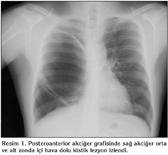

Yirmi be? ya??ndaki erkek hasta rutin ?ekilen postero-anterior akci?er grafisinde sa? akci?er orta ve alt zonda i?i hava dolu kistik lezyon izlenmesi ?zerine ?ekilen bilgisayarl? tomografide sa? akci?erde her ?? lobdan k?ken alan birbirlerinden atelektazik akci?er dokusu ve inkomplet maj?r fiss?r ile ayr?lan ince duvarl? kontrastlanma g?stermeyen ?? adet dev kistik lezyon izlendi (Resim 1,2). ?z ge?mi?inde yar?k dudaktan opere oldu?u anla??ld?. Dev b?l ?n tan?s?yla opere edildi. Operasyonda kistik alanlar total eksize edilip bas? alt?ndaki akci?er parankimi serbestle?tirildi (Resim 3). Patolojik olarak bronkojenik kist tan?s? do?ruland?.

Resim 1